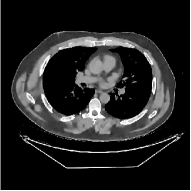

This section compares the reconstruction quality and runtime among the proposed MBIR method, PWLS-ST-, and other three MBIR methods, PWLS-EP, PWLS-DL, and PWLS-ST-. Table I shows that, for both 2D and 3D sparse-view CT reconstructions of the XCAT phantom, the proposed PWLS-ST- model outperforms PWLS-EP and PWLS-ST- in terms of RMSE. In addition, PWLS-ST- using a square transform (of size ) achieves lower RMSE than PWLS-DL using an overcomplete dictionary (of size ) for 2D sparse-view reconstructions. Fig. 3(a) and Fig. 4 show the reconstructed images for 2D and 3D phantom experiments, with different reconstruction models and different number of views. (See the corresponding error maps in the supplement.) The proposed PWLS-ST- consistently gives more accurate image reconstructions compared to other MBIR methods. Specifically, PWLS-ST- has smaller errors in the heart region (see zoom-ins in Fig. 3(a)) of 2D reconstructions than PWLS-DL and PWLS-ST-. In addition, compared to PWLS-ST-, PWLS-DL and PWLS-ST- have some ringing artifacts around the edges with high transition, e.g., edges between air and soft tissues. (See a comparison of profiles of PWLS-ST- and PWLS-ST- in the supplement.) In particular, PWLS-ST- and PWLS-DL give more visible ringing artifacts for 2D reconstruction from fewer views, and PWLS-ST- has these ringing artifacts for 3D reconstructions regardless of the number of views (see zoom-ins in Fig. 4). Table II reports runtimes of different MBIR methods in reconstructing the -views XCAT phantom scan. (FBPConvNet is a non-MBIR method and its runtime for processing a image is approximately one second with a TITAN Xp GPU.) While providing better reconstruction quality, the proposed Algorithm 1 of PWLS-ST- has shorter runtime compared to the algorithms of PWLS-DL and PWLS-ST- in Section III-A. Similar to the PWLS-EP algorithm, the reconstruction time of the PWLS-DL, PWLS-ST-, and PWLS-ST- algorithms can be further reduced by using ordered subsets [51].

Fig. 3(b) shows that when tested on the clinical scan data, the proposed PWLS-ST- method improves reconstruction quality in terms of noise and artifacts removal (e.g., see zoom-ins for soft-issue regions), and edge preservation (e.g., see zoom-ins for bone regions), compared to PWLS-EP and PWLS-ST-. Compared to PWLS-DL, PWLS-ST- achieves comparable image quality, but requires less computational complexity.

The benefit of the proposed PWLS-ST- over PWLS-ST- can be explained when there exist some outliers for some : in (12) gives equal emphasis to all sparse codes – from small to large coefficients that generally correspond to edges in low- and high-contrast regions, respectively – in estimating ; however, PWLS-ST- adjusts to mainly minimize the outliers, i.e., it may not pay enough attention to reconstruct regions with small coefficients. The histogram results in Fig. 1 reveal model mismatch of PWLS-ST- over the iterations. Fig. 3, Fig. 4, and Table I show that PWLS-ST- can moderate model mismatch, and provides more accurate reconstruction than PWLS-ST-.

| (a) 2D fan-beam CT experiments |

| (b) 3D axial cone-beam CT experiments |